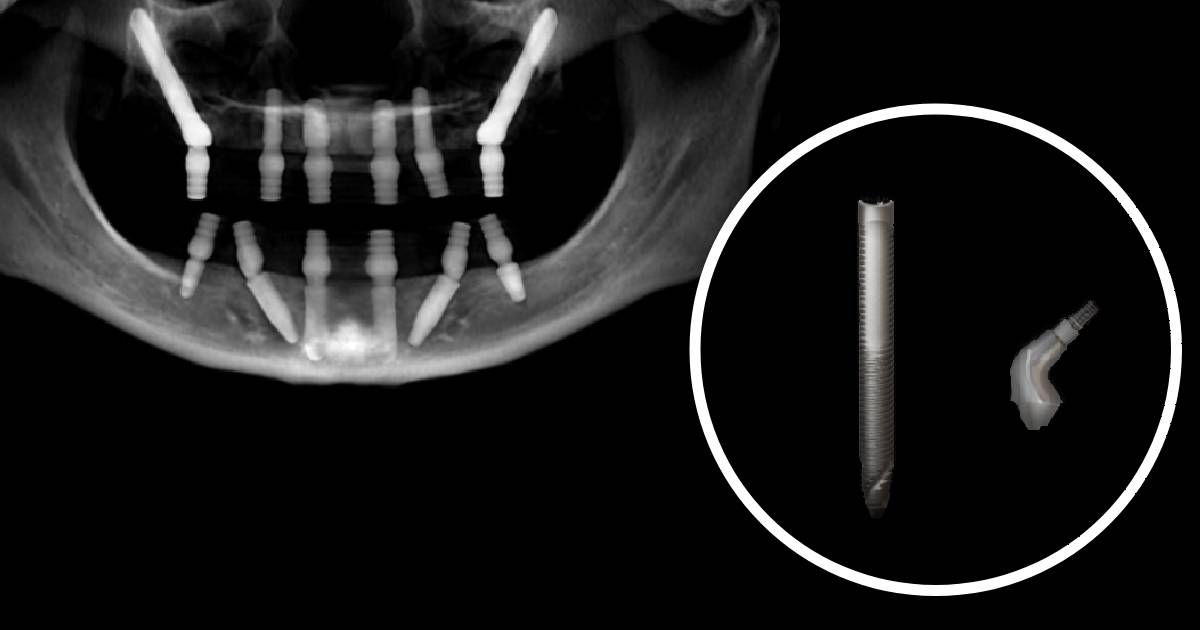

Zygomatic Bone Dental Implants . Single piece zygomatic implant, or a remote anchorage implant, is an effective tool for the rehabilitation of the atrophic/resected jaws. When indicated, zygomatic implants can offer a graftless approach to patients with severely atrophic maxilla. The time from surgical intervention to final prosthetic restoration can be shortened with the use of zygomatic implants. Unlike traditional implants that are anchored into. An anatomically based fixed solution for patients with atrophic maxillae, designed by experts with the patient in. Zygomatic implants are a type of dental implant specifically designed for patients with severe bone loss in the upper jaw. Zygomatic implants are an alternative when the maxillary bone is completely or partially absent, secondary to failure of. Zygomatic dental implants provide a lifeline for individuals facing severe bone loss in the upper jaw, making it possible for them to regain their smiles, confidence, and quality.